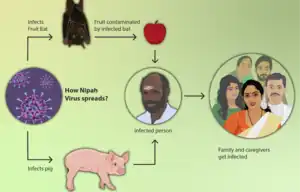

The initial case in human outbreaks of Nipah virus has always been zoonotic[8] from exposure to contaminated secretions or tissues of infected bats or pigs. Subsequent human-to-human transmission of Nipah virus occurs via close contact with NiV-infected persons or exposure to NiV-infected body fluids (e.g., blood, urine, nasal secretions).[1]

The risk of exposure is high for hospital workers and caretakers of those infected with the virus. In Malaysia and Singapore, Nipah virus infected people with close contact to infected pigs. In Bangladesh and India, the disease has been linked to consumption of raw date palm sap (toddy), eating of fruits partially consumed by bats, and using water from wells inhabited by bats.[11][12]

How the Nipah virus spreads[13]

How the Nipah virus spreads[13] Fruit bats are the natural reservoirs of Nipah virus

Fruit bats are the natural reservoirs of Nipah virus

Prevention through sanitary practices is the best protection. The likelihood of infection through animal transmission can be reduced by avoiding exposure to sick pigs, and to bats where the disease is endemic. Bats harbor a significantly higher proportion of zoonotic viruses than all other mammalian orders,[14] and are known not to be affected by the many viruses they carry, apparently due to their developing special immune systems to deal with the stress of flying.[15] Infection via bats can be caused by drinking raw palm sap (palm toddy) contaminated by bat excreta,[16] eating fruits partially consumed by bats, and using water from wells infested by bats.[12] Bats are known to drink toddy that is collected in open containers, and occasionally urinate in it, which contaminates it with the virus.[16]